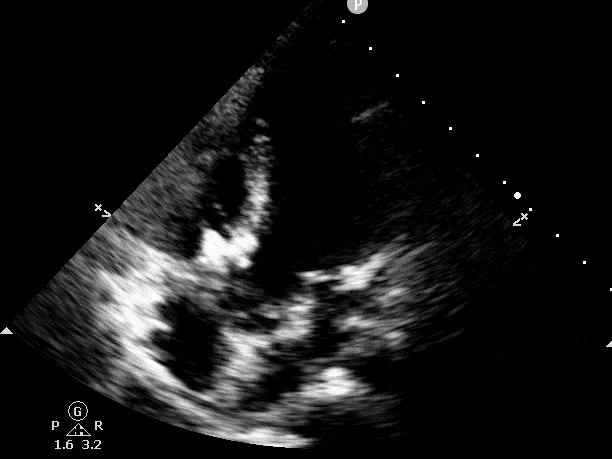

牵拉试验,封堵器稳定无移位,释放封堵器后超声下确认无残余分流,无主动脉瓣反流,三尖瓣反流同术前无增加。

大动脉短轴切面,封堵器释放后双盘紧贴间隔,呈现完美“工字形蝴蝶形”,顺应VSD形态及瓣膜形态。

MemoSorb全降解VSD封堵器展现了极佳的顺应性,在通过长隧道、小出口的VSD后,能顺利从“长哑铃”形态展开并固定为贴壁良好的“蝴蝶”形态。术后即刻超声评估显示,伞盘封堵完全,对相邻瓣膜无任何影响,主动脉瓣及三尖瓣均未出现反流。

术后24小时随访:

超声提示:

室缺封堵术后:

封堵器位置固定,室水平未见明显分流

左室整体收缩功能正常

右室收缩功能正常

两次随访中,MemoSorb全降解封堵器形态稳定、无位移、无残余分流、无主动脉瓣反流,三尖瓣反流与术前无明显差异。